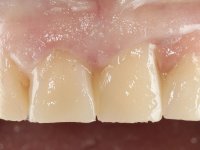

Female patient, 47 years old non-smoker. Tooth 1.3 with endodontic treatment and a cast post and core, rehabilitated with a provisional crown. The two upper lateral incisors are conoid and of small dimension. Tooth 2.2 presents mobility, in agreement with a significant bone reabsorption between teeth 2.1 and 2.3. The two central incisors are separated by a 3 mm diastema and tooth 2.3 presents a crossed occlusion with the opposing tooth. There is also an absence of some posterior teeth and reasonable oral hygiene. In the second intervention performed 8 years later, it was verified that the upper central incisors were chromatically darker and had a longitudinal groove in the enamel which, being pigmented, aesthetically compromised the smile. The work performed in the first phase of the treatment was competent, aesthetically and functionally. Finally, one year after the last intervention, the patient complained of a fracture on the veneer placed on tooth 2.1, probably as a result of being in contact with the abutment of the implant. The rigidity of implant ankylosis may have been the cause of this fracture. I have observed other instances of this type of fracture in identical clinical situations. The veneer of tooth 1.2 was aesthetically compromised and the dental structure itself had small caries and, therefore, its replacement would be recommended.

Eight years later, in the second intervention, the following treatment was proposed:

• Restoration of teeth Superior Central Incisors with feldspathic ceramic veneers.

This addition of resin would guide the ceramist in the final placement of the gingival tonality ceramic. The crown that would rehabilitate tooth 1.3 was cemented in this test session with glass ionomer cement, reinforced with composite resin. Once the laboratory work was finished on the veneer for tooth 1.2, the abutment, and the veneer for the implant, this was bonded in the mouth, after placement of the absolute insulation. The work completely satisfied the patient. For eight years, the patient had periodical check-ups, and was pleased with the treatment, but also began to show interest in an aesthetical intervention on the upper central incisors. Once the second phase of our intervention was decided, dental preparation of teeth 1.1 and 2.1 was performed for the placement of two feldspathic veneers. Particular care was taken in the distal inter-proximal preparation adjacent to the abutment of the implant.